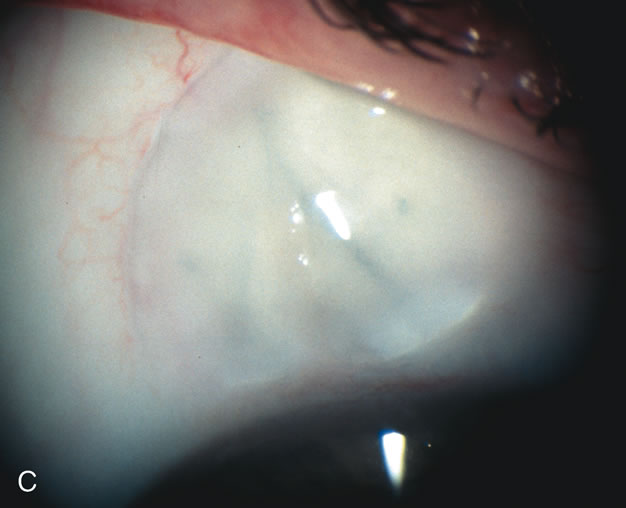

Table 1. Patients Who Are Candidates for Combined Cataract

Long-term IOP control after combined cataract-glaucoma surgery is better than cataract extraction alone. Combining a cataract extraction with a filtration procedure without using an antimetabolite, results in a long-term lowering of IOP slightly greater than that caused by cataract extraction alone.83–87 Long-term IOP control after phacotrabeculectomy is better than with ECCE-trabeculectomy, with fewer medications needed in the phacotrabeculectomy group.88 5-Fluorouracil (5-FU) does not improve the IOP-lowering effect of combined cataract and glaucoma surgery. Adjunctive use of 5-FU at the time of cataract extraction has, in the dosage and methods so far used, not appreciably improved the long-term pressure lowering associated with ECCE combined with a guarded filtration procedure.89–91 There also appears to be limited pressure-lowering benefit from postoperative 5-FU injections for combined same-site phacotrabeculectomy.92–94 There is limited data on the efficacy of intraoperative 5-FU for combined phacotrabeculectomy. Mitomycin-C (MMC) does improve the IOP-lowering effect of combined cataract and glaucoma surgery. Antimetabolite usage is worth the long-term risks of blebitis and hypotony in patients who are likely to go blind without its application. However, patients without advanced disc damage who can tolerate one or two postoperative glaucoma medications may not need an antimetabolite and certainly should not be exposed to high concentrations of MMC. Combined same-site phacotrabeculectomy with MMC lowers IOP more effectively with fewer postoperative medications and larger filtration blebs than without MMC.95–97 MMC also improves the success rate in blacks, eyes of patients on two or more glaucoma medications, eyes with IOP 20 mm Hg or higher, and prior failed trabeculectomy.98,99 Antimetabolite use in combined procedures is associated with a lower postoperative IOP with reduced need for long-term glaucoma medications.100 MMC appears to have a beneficial effect on long-term filtration surgery and on combined surgery without the corneal toxicity of 5-FU.101 However, long-term bleb morphology with MMC is different from that with 5-FU. Excessive concentrations or durations of MMC cause progressive conjunctival necrosis with bleb leaks, hypotony, and possible endophthalmitis. Antimetabolite usage has decreased with trabeculectomy surgery and is reserved for high-risk patients likely to scar down without its usage. COMBINED CATARACT AND GLAUCOMA SURGERY Phacotrabeculectomy is more effective than ECCE-trabeculectomy with or without postoperative 5-FU injections.102–105 The smaller incision associated with phacoemulsification likely leads to less intraocular inflammation and wound healing, allowing better bleb formation. Phacotrabeculectomy with intraoperative or postoperative 5-FU significantly lowers IOP but not as successfully as 5-FU trabeculectomy alone.106 This is probably related to the prolonged anterior chamber flare following phacoemulsification compared with trabeculectomy with peripheral iridectomy.107 Combined same-site phacoemulsification, posterior chamber IOL, and trabeculectomy without antimetabolite significantly lowers IOP.108–111 Results of same-site phacotrabeculectomy appear similar with either a 3.5-mm incision with a foldable IOL or a 5.2-mm incision with a rigid single piece PMMA lens.112,113 Phacotrabeculectomy with intraoperative 5-FU is as efficacious as a 5-FU trabeculectomy followed by phacoemulsification.114 Visual acuity and complications of combined phacotrabeculectomy are comparable to a two-staged approach with the obvious benefit of earlier visual rehabilitation.115 Foldable silicone lenses are associated with an increase in postoperative inflammation compared to PMMA lenses.116 SINGLE-SITE VERSUS TWO-SITE COMBINED CATARACT AND GLAUCOMA SURGERY Combined ECCE-trabeculectomy techniques now yield to smaller incision combined phacotrabeculectomy. The methods for combining phacotrabeculectomy vary, depending on physician training, preference and patient anatomy. For example, physicians with two-site experience will have an easier access to the surgical site in a patient with enophthalmos and a prominent brow who requires a combined procedure. A temporal approach for the lens extraction is much easier in this particular case. IOP control following one-site versus two-site phacotrabeculectomy with MMC is similar but with a trend for less postoperative glaucoma medications,117 improved IOP control,118 less induced astigmatism,119 and better bleb formation in the two-site group.120 CATARACT EXTRACTION CAUSES PARTIAL OR COMPLETE FAILURE OF EXISTING FILTERING BLEBS Cataract extraction by any technique performed in a patient with a pre-existing filter will have an effect on the previous filtering bleb.121–124 Bleb failure is more likely with ECCE compared with small-incision phacoemulsification.125 However, even patients undergoing topical anesthesia with clear corneal phacoemulsification and foldable IOL may experience bleb failure. One of three patients with a functioning filter and preoperative mean IOP of 12 mm Hg without antiglaucoma medications experiences bleb failure after lens extraction (Table 2). These patients require long-term drug therapy or bleb needling to control IOP. 126 Additional incisional glaucoma surgery may eventually be required in up to 10% of patients.127 Intraoperative iris manipulation may cause significant breakdown of the blood–aqueous barrier, resulting in inflammation that causes bleb failure. Even after uncomplicated clear corneal phacoemulsification, IOP may increase an average of 2 to 3 mm Hg due to bleb fibrosis.128 Approximately 20% of filtered patients require a long-term increase in glaucoma medications following uncomplicated clear corneal phacoemulsification with a foldable copolymer acrylic IOL129 (Fig. 3). In situations in which the bleb is not working at all, the eye will have a postoperative pressure spike that mimics that in the patient not having had a prior filtering procedure. In situations in which the bleb is marginal, the pressure spikes tend to be lower, and the final postoperative IOP tends to be around 50% higher than it was preoperatively. These patients require combined procedures in order to reestablish long-term filtration. In situations in which the bleb is very thin, polycystic, and associated with an IOP around 5 to 8 mm Hg on no antiglaucoma therapy; uncomplicated cataract extraction will have a minimal effect on the level of IOP. Patients with functioning glaucoma drainage implants usually have minimal long-term changes in IOP after uncomplicated cataract extraction.130